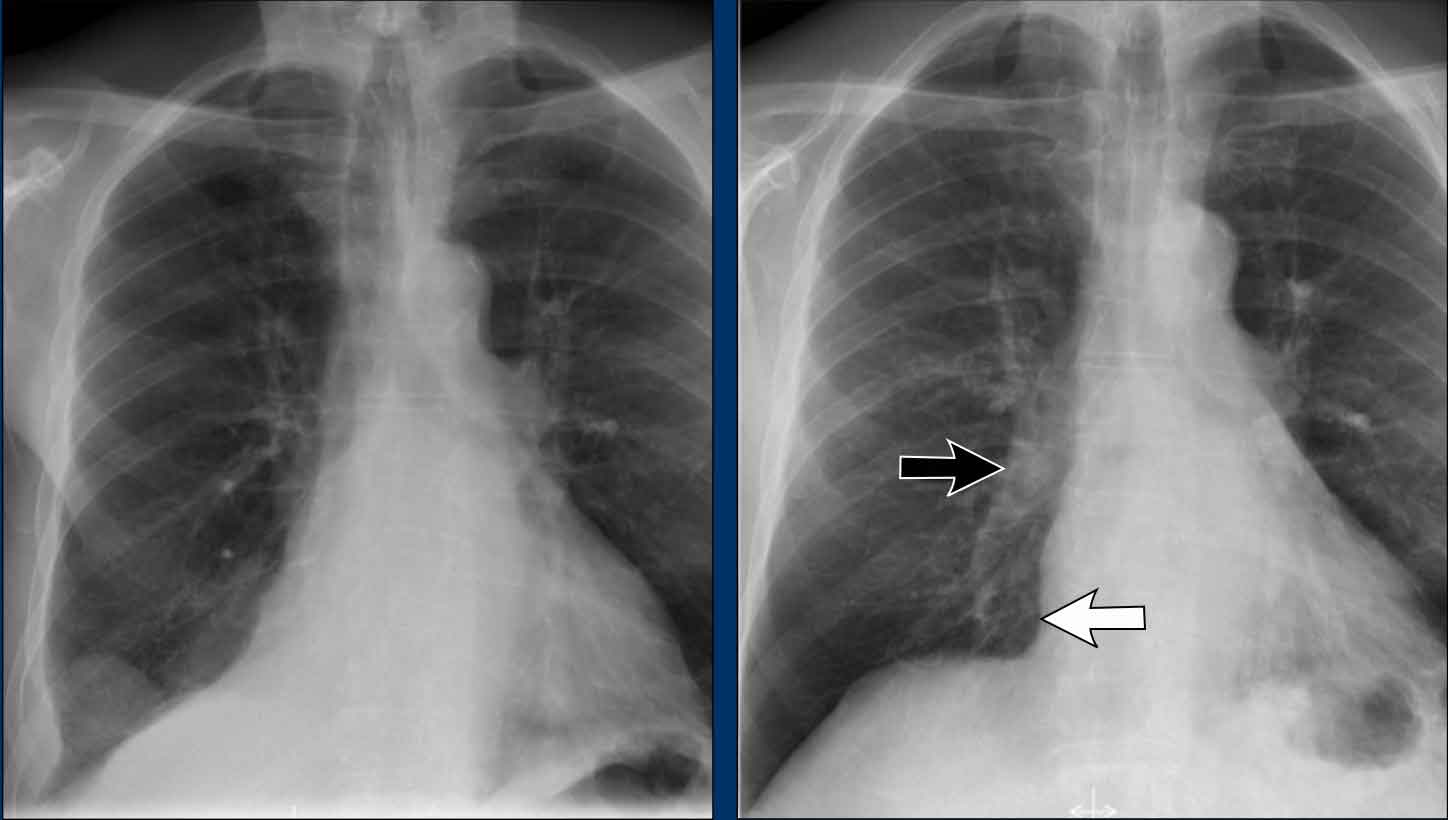

Clinical Case

A 70-year-old male patient presents following a fall down the stairs, complaining of severe right flank pain.

Imaging Findings

• On the PA chest radiograph, there is an absence of the right fifth digit.

• On the lateral view, there is increased density projected over the lower thoracic spine.

What is your diagnosis?

The findings are consistent with right lower lobe atelectasis.

On the PA view, note the abnormal contour of the right heart border. The right interlobar pulmonary artery is not visualized—this is because it is not surrounded by aerated lung, but rather by the collapsed right lower lobe, which lies adjacent to the right atrium.

On follow-up imaging, the right lower lobe has re-expanded, and the atelectasis has resolved.

This suggests that the atelectasis was likely due to post-traumatic hypoventilation with mucus plugging.

Also noted on the follow-up radiograph is the reappearance of the right fifth finger (black arrow), and restoration of a normal right heart border (white arrow), confirming re-expansion of the lower lobe.